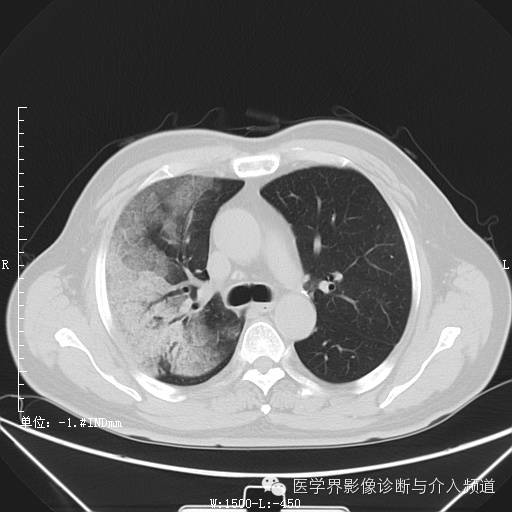

初诊

初诊:右肺上叶见大片实变影,呈磨玻璃状及网状,可见“充气支气管征”,纵隔窗可见实变影范围有所缩小,呈蜂窝状,局部支气管走行不自然,管壁不光滑。